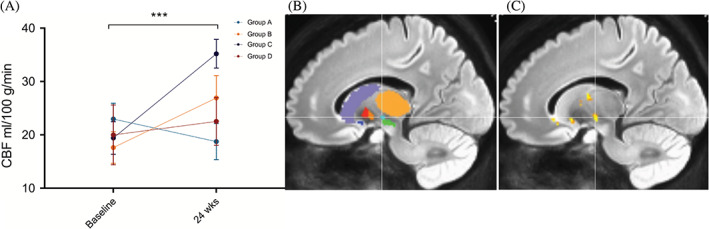

偽連續(xù)動脈旋轉(zhuǎn)顯示時間( P<0.001)和區(qū)域(P<0.001)的主效應(yīng)顯著,但半球( P=0.401)或隊列(P=0.088)?的主效應(yīng)不顯著。所有基底神經(jīng)節(jié)結(jié)構(gòu)的灌注從基線到輸注后24周總體增加。事后按區(qū)域時間比較顯示,同種異體hMSC輸注后,隨時間變化的灌注增加最顯著的是丘腦底核(圖2)。

方法:德克薩斯大學休斯頓健康科學中心神經(jīng)內(nèi)科在輕度至中度PD患者中進行了一項單中心、開放標簽、遞增劑量遞增的 1 期臨床研究。20名參與者依次進入4個劑量組中的1個并接受單次靜脈輸注:A組,1×106allo-hMSCs/kg;B組,3×106allo-hMSCs/kg;C組,6×106allo-hMSCs/kg;和D組,10×106allo-hMSCs/kg。受試者在輸注后第3、12、24 和52周返回進行評估。